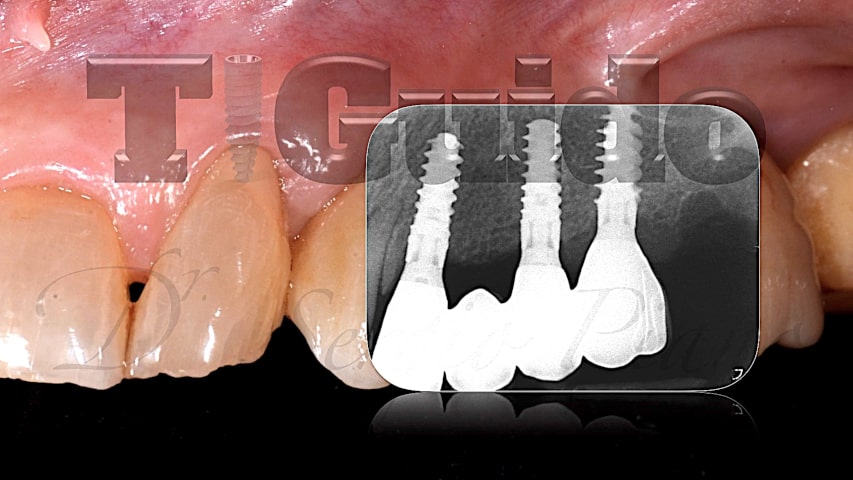

Uno dei punti chiave dell’implantologia computer-guidata è la possibilità di fare una programmazione combinando i dati dell’anatomia ossea con quelli della situazione dentale iniziale e quelli della previsualizzazione finale. In questo modo si possono posizionare gli impianti con grande accuratezza nel rispetto dei volumi ossei e degli spazi protesici, si può pianificare la disposizione e l’emergenza degli abutment e si possono determinare le forme dei provvisori adeguandoli perfettamente alla disposizione implantare.

Implantologia in siti post-estrattivi ed in presenza di difetti ossei: l’utilizzo della dima chirurgica guida strettamente la fresa lungo l’asse predeterminato, impedendo lo scivolamento verso le zone di minor resistenza e permettendo un posizionamento implantare ottimale

Protesizzazione immediata e carico immediato: la precisa pianificazione consente una ideale collocazione dei fori delle viti protesiche ed una drastica riduzione dei tempi di adattamento protesico alla poltrona

Uso di impianti inclinati per evitare ostacoli anatomici: consente la riabilitazione di pazienti con supporto osseo residuo ridotto senza dover ricorrere ad interventi di chirurgia rigenerativa che sono dispendiosi in termini di tempo, costo e comfort per il paziente; è possibile determinare in fase di progettazione anche l’emergenza e la direzione degli abutment angolati per una protesizzazione avvitata senza compromessi